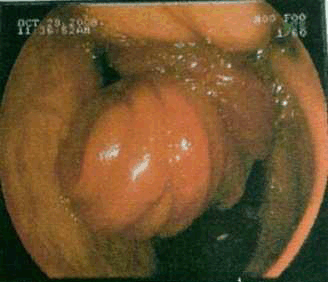

A 50-year-old female patient presented to ESI-PGIMSR with complaints of acute abdominal pain, vomiting and mass in the upper abdomen since four days. She had undergone gastrojejunostomy and truncal vagotomy for chronic duodenal ulcer twenty years back. On physical examination, the patient was dehydrated with pulse rate of 108/minute, blood pressure of 100/60 mmHg and respiratory rate of 18/min. Abdominal examination revealed upper midline abdominal scar of previous laparotomy. A tender sausage shaped lump was palpable in the umbilical region measuring 10x5 cm which moved with respiration (figure 1). Laboratory investigations showed hemoglobin of 9.3 gm%. After correction of dehydration and electrolyte imbalance, an emergency upper gastrointestinal endoscopy was carried out which revealed an intussusception of small bowel at gastro-jejunal anastomosis (figure 2). Computed tomography (CT) scan of the abdomen and pelvis revealed retrograde jejuno-gastric intussusception through previous gastrojejunostomy with edematous walls of intussusception and minimal ascites (figure 3). After initial treatment with intravenous fluids, nasogastric suction and antibiotics, emergency exploratory laparotomy was carried out.

Figure 2: Endoscopic photograph showing intussuscepted mass sharply demarcated and normal gastric mucosa.